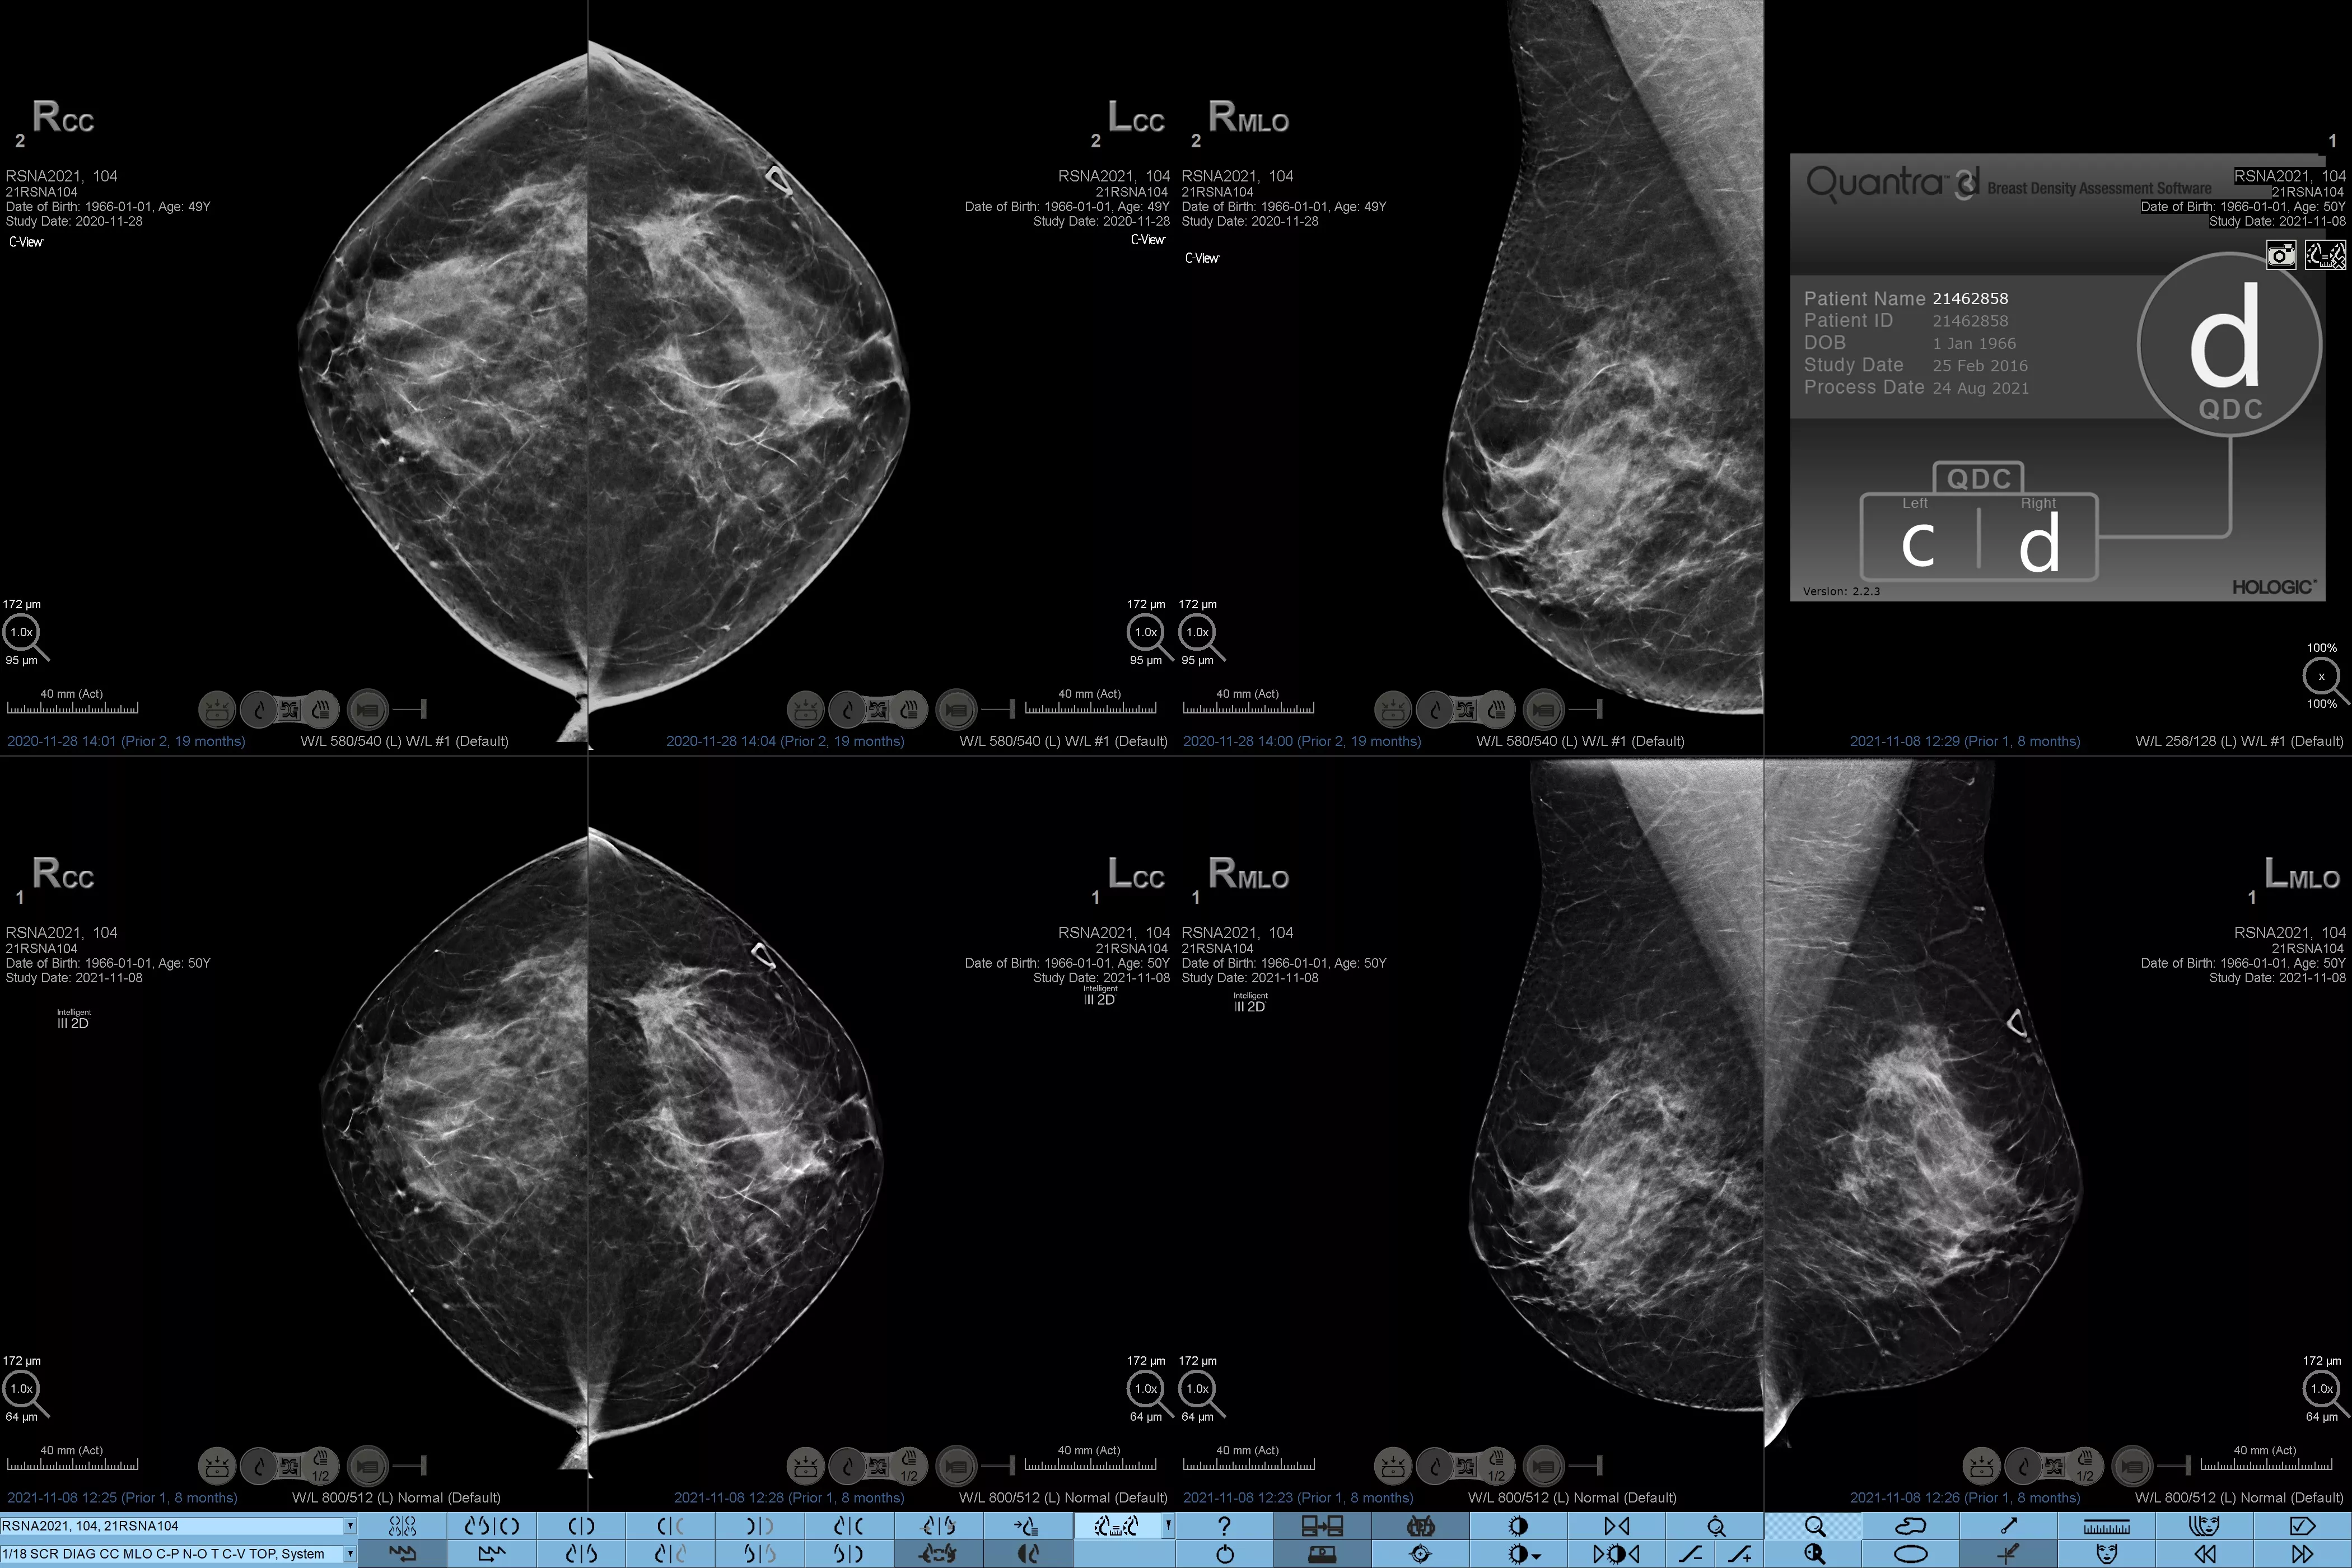

Higher breast density is known to increase a woman’s risk for breast cancer.1 The need for accurate, unbiased analysis is therefore critical. Powered by machine learning, Quantra technology software analyses both 2D™ and tomosynthesis images for distribution and texture of parenchymal tissue. It categorises breasts in four breast composition categories consistent with guidance from the American College of Radiology (ACR) BI-RADS Atlas 5th Edition.2

Objective machine learning algorithm that assigns breast density category based on analysis of breast tissue texture and patterns.

Quantra software’s unbiased algorithm analyse both 2D and tomosynthesis images to support your analysis by:

• Overcoming subjectivity in visual assessment, providing more consistent, and more reliable scoring.*

*Scores are based on ACR BI-RADS categories, in line with the revised guidance by the American College of Radiation (ACR) BI-RADS Atlas 5th Edition. This accounts for pattern and texture, compared with volume, when determining density.